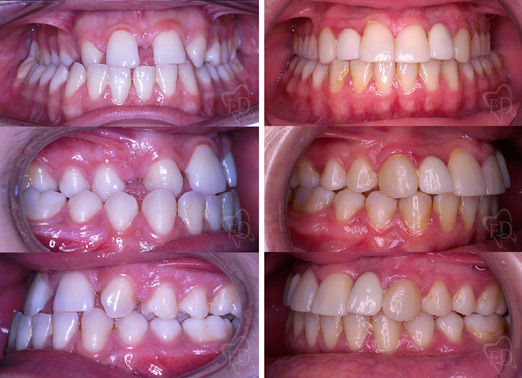

II classe con estrazioni:

prima dopo